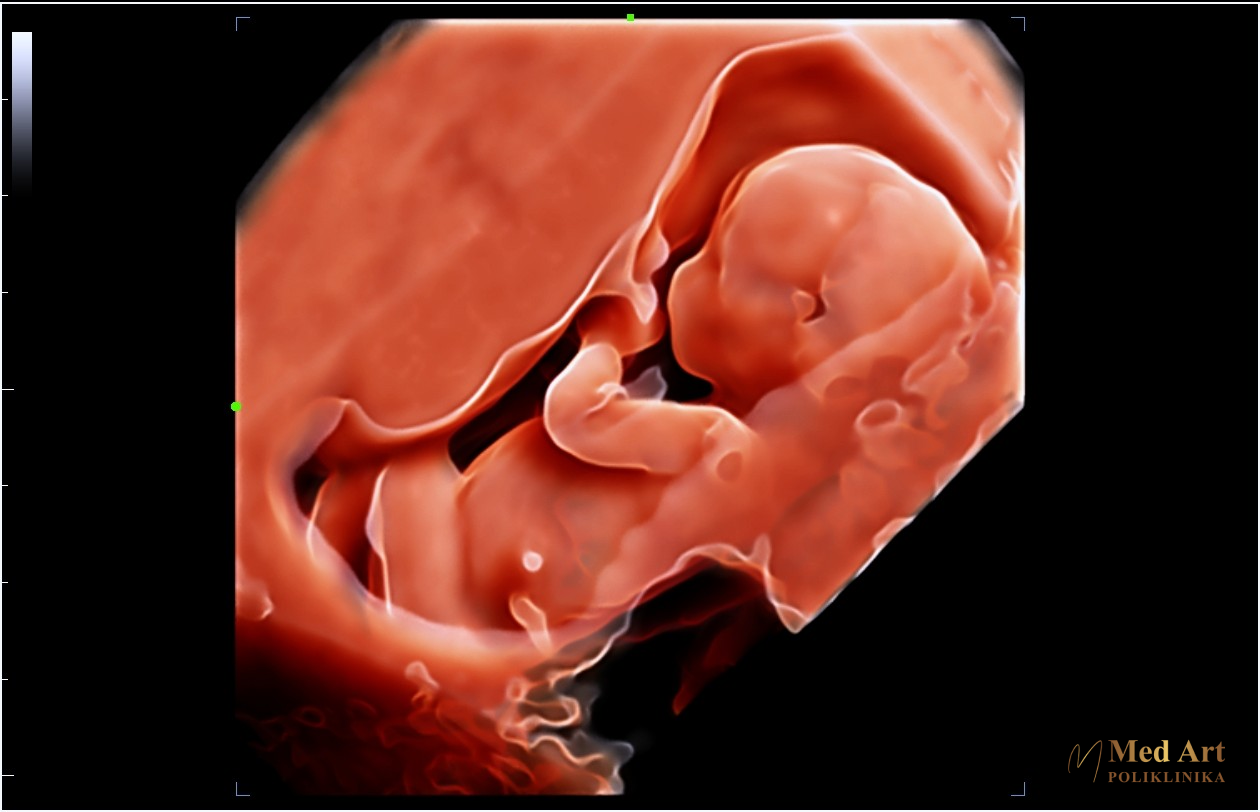

U galeriji koja slijedi, možete vidjeti ultrazvučne slike beba u 6., 7., 8., 12., 14., 20., 21., 24., 27. i 34. tjednu trudnoće, koje prikazuju njihov razvoj od rane trudnoće pa sve do priprema za dolazak na svijet.